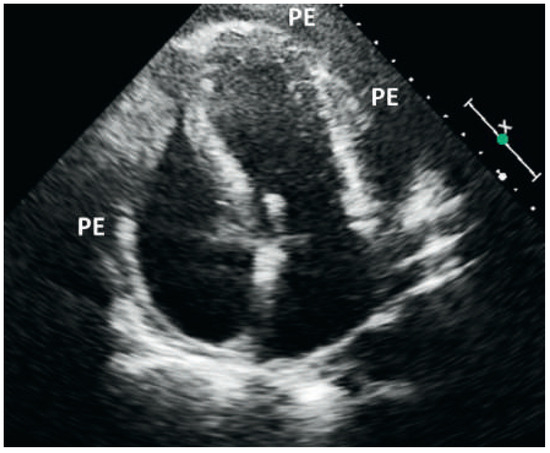

Kussmaul's Sign in Effusive Constrictive Pericarditis

by Mattia Cattaneo, Stefano Muzzarelli, Francesco Faletra, Alessandra Pia Porretta, Francesco Siclari and Augusto Gallino

Cardiovasc. Med. 2015, 18(1), 32; https://doi.org/10.4414/cvm.2015.00296 - 21 Jan 2015

A 67-year old man with mitral valve prolapse and moderate regurgitation was admitted because of dyspnoea, bilateral ankle swelling and hypotension. Close inspection of the jugular veins identified Kussmaul’s sign, a typical increase in the central venous pressure during inspiration (fig. 1; arrows) [...] Read more.

A 67-year old man with mitral valve prolapse and moderate regurgitation was admitted because of dyspnoea, bilateral ankle swelling and hypotension. Close inspection of the jugular veins identified Kussmaul’s sign, a typical increase in the central venous pressure during inspiration (fig. 1; arrows) [...]